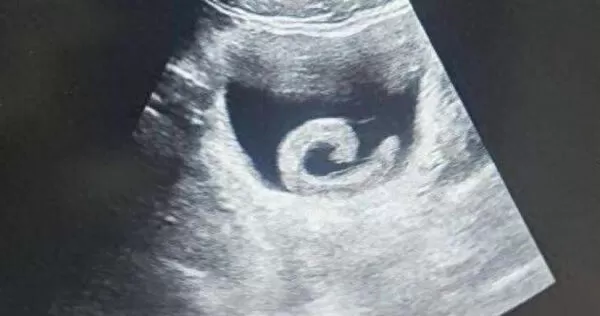

▲水蛭緊緊吸附在男子的膀胱黏膜。(圖/翻攝自微博)

根據《大河報》報導,小鄭起初並未察覺異狀,還對可能產生的「特殊體驗」抱有期待,但不久後便出現劇烈疼痛與排尿困難等症狀,嚇得趕緊前往鄭州市人民醫院求診。醫生檢查發現,水蛭沿著尿道向內爬行,最終進入膀胱並附著吸血,同時分泌抗凝血物質,導致症狀迅速惡化。

經檢查後,泌尿外科副主任醫師馬曜輝為患者施行經尿道膀胱異物取出手術,所幸過程順利,尿道阻塞的狀況獲得解除,疼痛隨即緩解。小鄭事後坦言,對自己的魯莽行為感到後怕與懊悔。